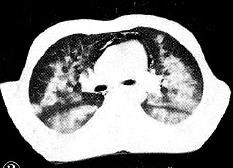

1.青年患者,诉气促,CT如下:

病灶也是沿着肺门对称分布,但是这对蝴蝶翅膀太大。追问病史,吸毒,生活很乱,查HIV阳性。

原来是卡氏肺孢子虫肺炎。注意,胸膜下无明显侵犯,是其特点。